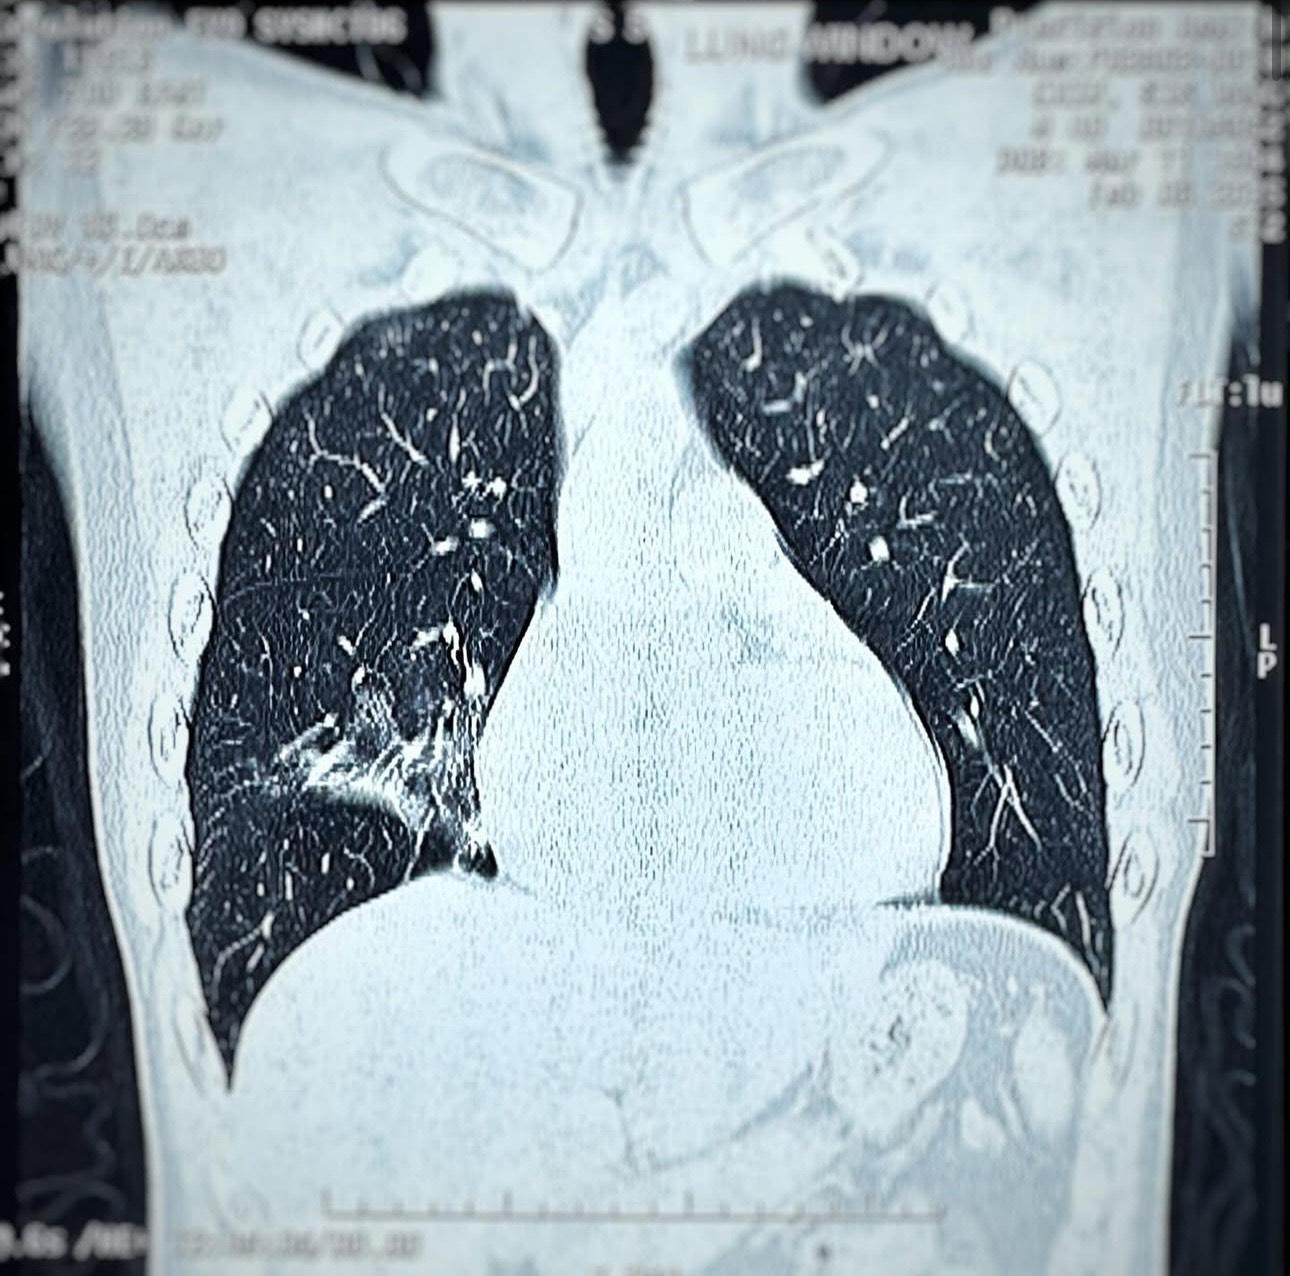

恆仔在社交網透露由年初一開始狂咳到而家,他表示︰「聽(今)日有兩場show,仲咳緊,深呼吸到丹田嘅話右邊就會有少少痛同埋咳出嚟,頂硬上勉強應該唱到嘅,怕係怕影響之後,所以睇清楚。依家confirm咗冇中任何流感,但個肺花咗少少。我唔會失場,但可能會有少少失準,聽日見!」他續公開照肺部的X光片,發現右邊肺有肺花,他表示︰「1. 左邊無嘢,右邊有花。醫生話依家都好普遍,唔使太擔心。食足抗生素,準時食藥,瞓多啲覺,會好番。2. 幾萬種流感,全部Negative,但聽日同我影相都帶番個口罩。大家真係要身體健康,著多件衫,唔好凍親。冇咩就瞓多啲覺,流感高峰期過咗再玩過。#咳到橫膈膜都痛」不少圈中好友都紛紛留言叫他保重身體。